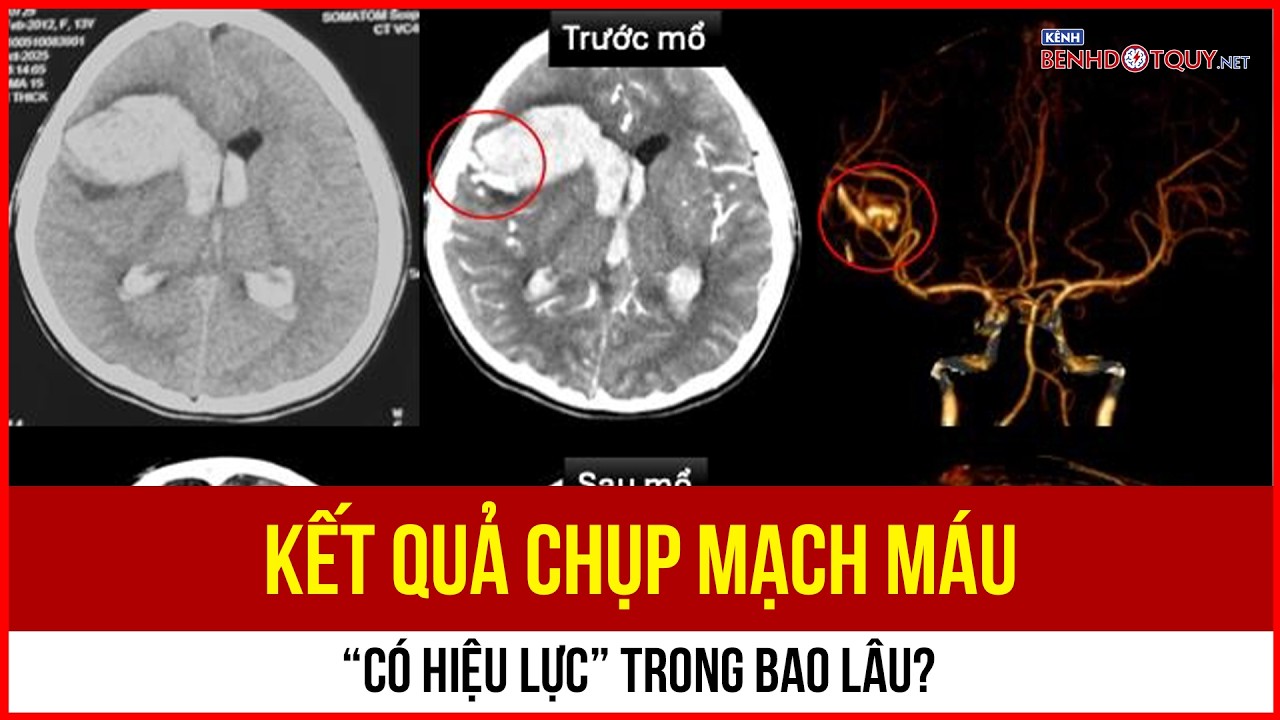

Khuya 19/8/2025, cụ bà 79 tuổi nhập viện trong tình trạng đau đầu dữ dội, có tiền sử tăng huyết áp. Ngay lập tức, ekip khoa Nội Thần kinh – Đột quỵ tiến hành chụp CT não và CTA mạch máu não, phát hiện xuất huyết dưới nhện do túi phình động mạch não đoạn C7 kích thước 3×5×5 mm vỡ.

Nhận thấy tình trạng nguy cấp, ekip can thiệp lập tức được kích hoạt. Trong vòng 45 phút, các bác sĩ đã bít coil túi phình thành công, ngăn chặn nguy cơ xuất huyết tái phát, đồng thời bảo tồn tối đa chức năng não bộ cho bệnh nhân.

Sau can thiệp, bệnh nhân tỉnh táo, giảm đau đầu rõ rệt (Ảnh: BSCC)